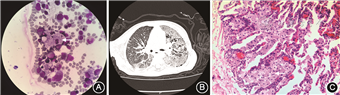

患儿 男,3岁1月龄。因“反复喉间痰鸣4个月”于2017年4月就诊于浙江大学医学院附属儿童医院呼吸科。患儿4个月前出现喉间痰鸣,单声咳嗽,未至医院就诊,在家中间断口服头孢克肟(具体疗程及药物剂量不详),仍有喉间痰鸣。9 d前出现2次间断发热,体温波动在37.0~38.1 ℃,每次发热1~2 d,当地医院胸部X线片提示“支气管肺炎”,先后给予“阿奇霉素及头孢曲松”静脉滴注治疗1周,喉间痰鸣减轻,复查胸X线片示“肺炎征象无好转”,遂至浙江大学医学院附属儿童医院门诊就诊,拟诊“慢性肺炎”收住院。患儿2015年1月因“血小板减少”在浙江大学医学院附属儿童医院门诊就诊,骨髓常规示巨核细胞增多,产血小板功能差,涂片中找到大量泡沫状细胞,疑为尼曼-匹克细胞(图1A)。既往多次因“肺炎”住院,曾于2015年8月诊断“重症肺炎,呼吸衰竭Ⅱ型,间质性肺病”于浙江大学医学院附属儿童医院呼吸科住院治疗,查胸部CT示“两肺散在斑片影及细网格样改变”,此后多次随访,复查胸X线片未见好转。患儿系其母第3胎第3产,足月自然出生,出生体重2.8 kg,生后无窒息抢救史、无高胆红素血症病史。2岁内生长发育同正常同龄儿;3岁时发现走路不稳,说话不能成句。父母非近亲婚配。大姐21岁,体健;二姐患有“癫痫”,7岁时死亡(具体不详)。

辅助检查:血常规示白细胞11.2×109/L,中性粒细胞0.60,嗜酸粒细胞0.02,血红蛋白133 g/L,血小板140×109/L,C反应蛋白2 mg/L。肝肾功能、过敏源及免疫球蛋白、T细胞亚群均未见异常。结核感染T细胞斑点检测、自身抗体20项、EB病毒抗体、巨细胞病毒抗体、1, 3-β-D葡聚糖试验、半乳甘露聚糖试验、呼吸道病毒免疫荧光7项、肺炎支原体RNA、痰细菌及念珠菌、曲霉菌培养、巨细胞病毒DNA均阴性。胸部CT示两肺大部呈磨玻璃状,内见支气管充气征及多发小囊状透亮区,小叶间隔增厚(图1B)。头颅磁共振成像示双侧脑室体后部斑片状长T2信号影,胼胝体偏薄,其余未见异常。腹部超声示脾脏肋间厚3.5 cm,肋下4.5 cm。入院第6天行纤维支气管镜检查及灌洗治疗,镜下见气管及各支气管管腔通畅,黏膜充血水肿,管腔内见少许白色黏稠分泌物,予生理盐水灌洗,洗出黏液栓样液体。入院第9天行胸腔镜下肺活检,病理示镜下见肺泡区域间隔增宽,泡沫细胞浸润及纤维组织增生,肺泡腔内见大片泡沫状细胞(图1C)。北京协和医院病理科会诊示(左上肺)肺泡腔及间质内见大量泡沫状细胞聚集,病变以小叶周边部位分布为主,部分间质增宽,病变符合脂质性肺炎,倾向内源性,需要除外先天性基因及代谢异常;免疫组化示AE1/AE3(-),CD163(+),CD68(+),S-100(+);糖原染色阴性。